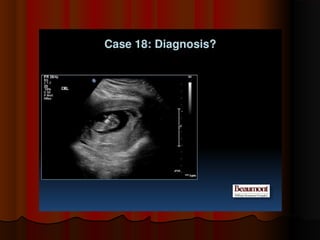

????????